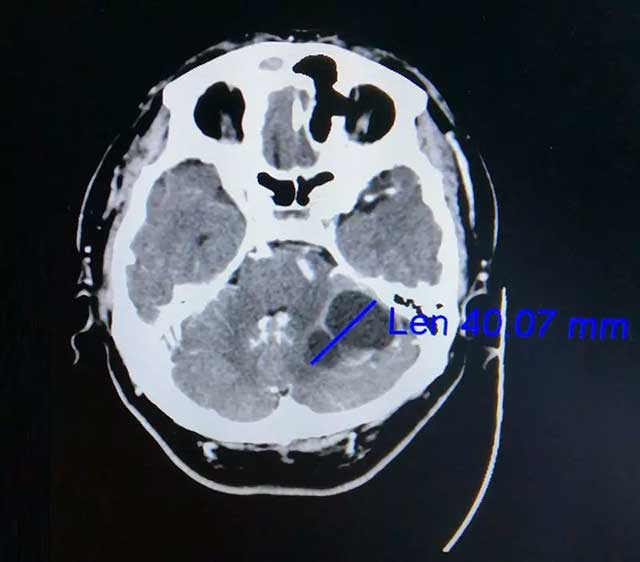

在家人陪伴下,劭阿伯到醫(yī)院做了檢查。查頭顱CT提示:左側(cè)小腦囊實(shí)性占位,很可能是轉(zhuǎn)移瘤。后又經(jīng)PET-CT檢查提示:左側(cè)小腦半球不規(guī)則囊性占位,轉(zhuǎn)移可能性大,原發(fā)腫瘤待排。此時(shí)懸在劭阿伯心中的“達(dá)摩克利斯之劍”搖搖欲墜,原來(lái)兩年前劭阿伯曾患肺癌,接受過(guò)放化療。為尋求進(jìn)一步治療,劭阿伯一家慕名來(lái)到上海藍(lán)十字腦科醫(yī)院。

▲ 增強(qiáng)CT顯示腫瘤達(dá)4公分大小